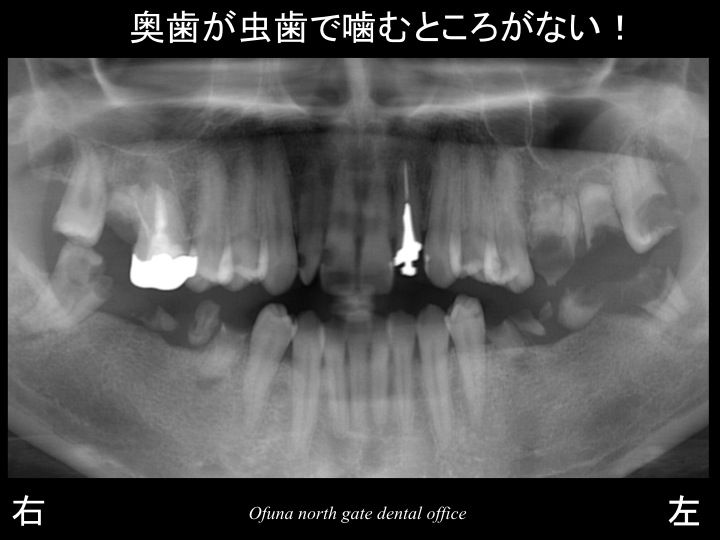

以下は初診時のレントゲンです。

始めて見られる方のために 簡単に以下のレントゲンの見方

について説明します。

以下のレントゲンの下に 右、左と書いてありますが、

当然のことながら 右と書いてあるのが“ 右側 ”です。

実際の左右とは違いますので、今後見られる時にはご注意下さい。

虫歯がいっぱいあることが分かるかと思います。

このように多くの虫歯がある方がいらっしゃいます。

今回の患者様は、

「虫歯あ多くあり、噛むところがない!」

とのことで来院された患者様です。

多くの歯が抜歯となるような状態です。